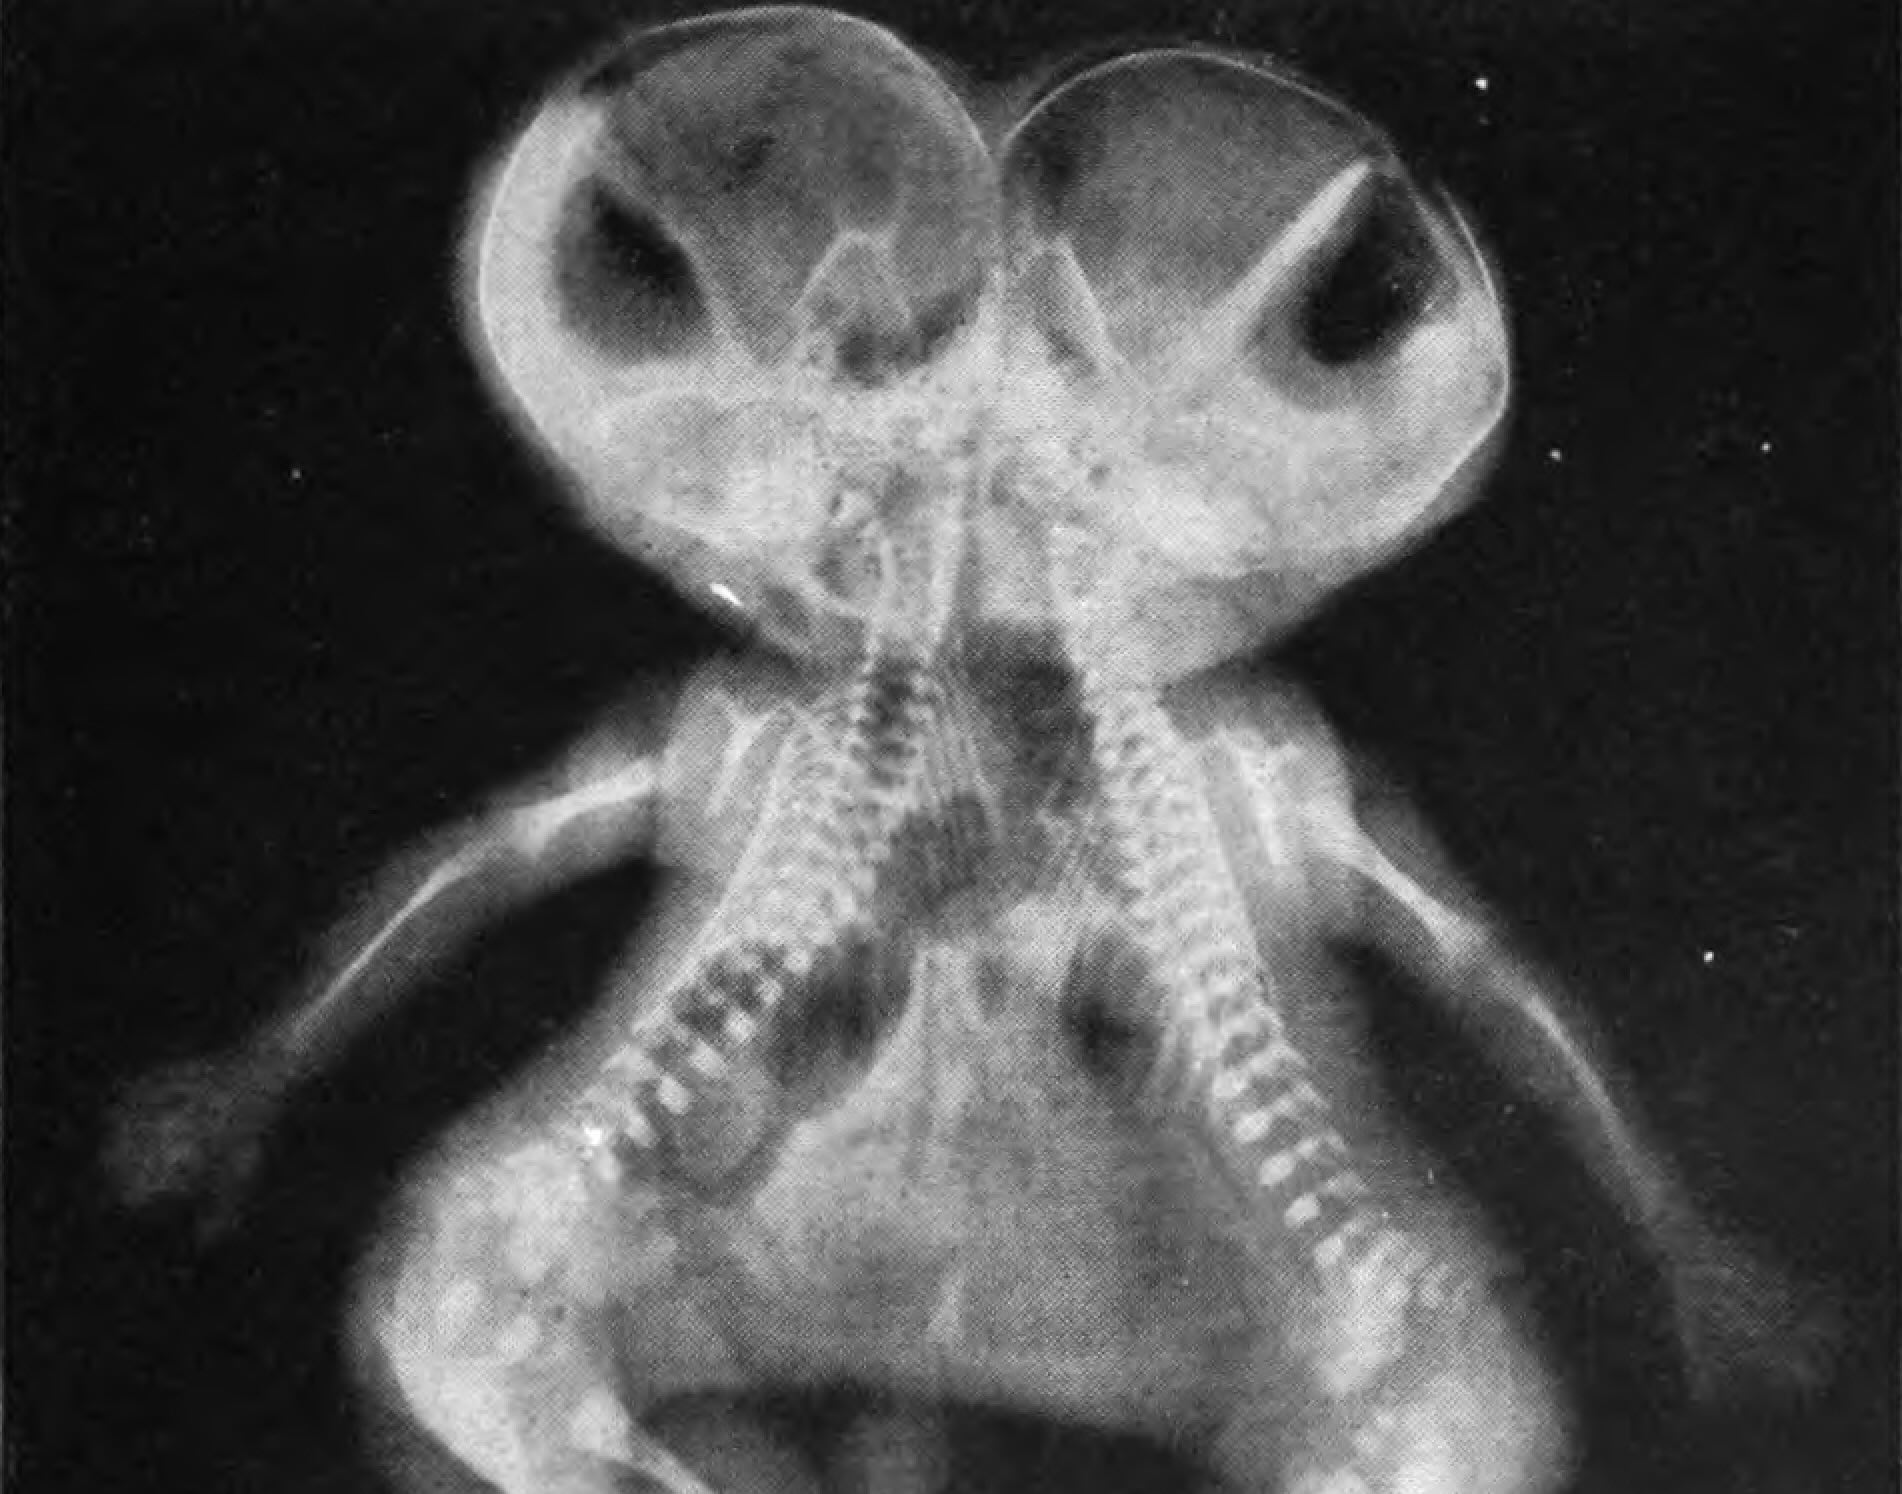

Photo by Mae M. Bookmiller, Public domain, via Wikimedia Commons